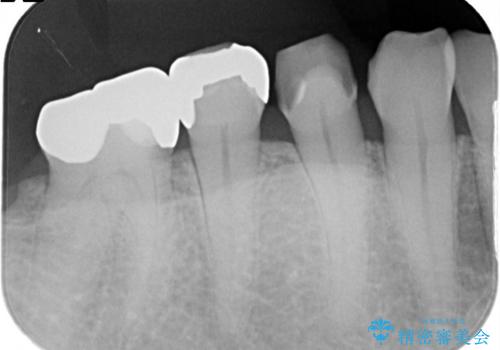

- 他院で治療した金属の詰め物が外れたことを主訴に来院されました。

PGAインレーにて修復治療を行いました。

ゴールドインレーは適合が良く、割れることもないため、長期的に安定した治療法となります。